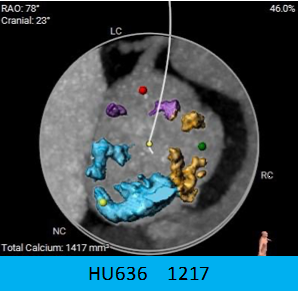

1.主动脉瓣瓣环周长90.9mm,平均周长径28.9mm。

2.CT数据显示该患者为TYPE1二叶式主动脉瓣,重度钙化,钙化分布不均,钙化沿无冠瓣叶及管壁附着缘分布,左右瓣之间有黏连钙化。

3.左冠开口高度偏低,瓣叶较长,冠脉风险较高,右冠高度可。

4.横位心,主动脉弓宽度偏小及角度锐角。双侧血管内径可,符合血管入路条件。

主动脉根部评估:

瓣环上解剖及钙化分布: